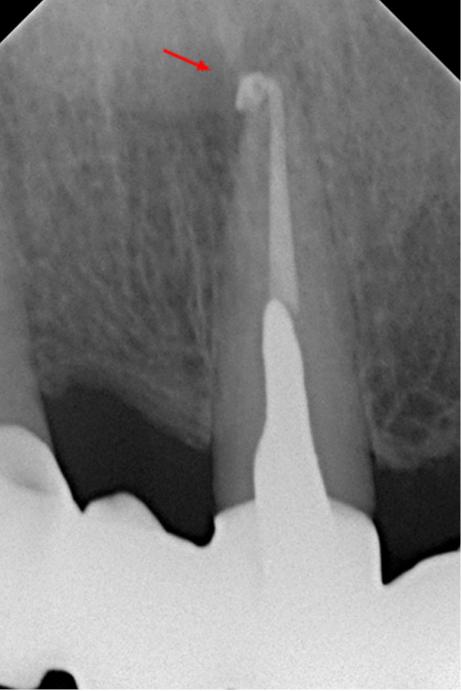

На контрольном снимке через 12 месяцев после лечения отмечается репарация тканей в области верхушки 21 зуба (снимок 4). Жалобы отсутствуют.